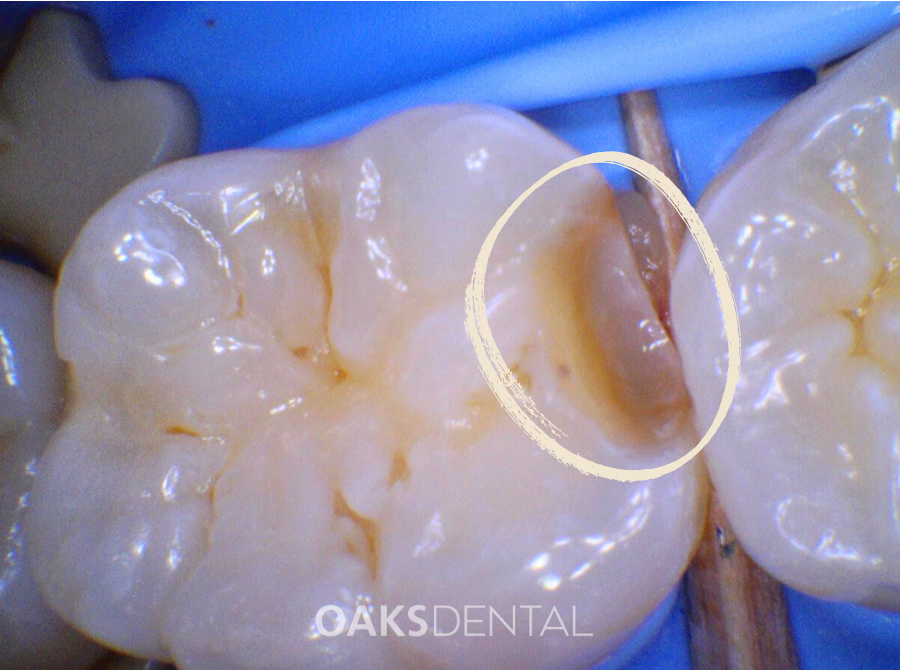

• A visible hole or dark spot on a tooth

A dental examination and X-ray remain the most reliable ways to assess whether a filling is required.